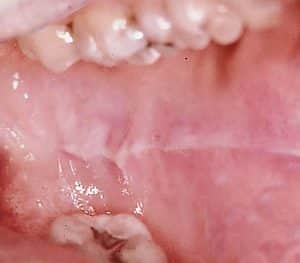

Lippen-/Wangenbeißen